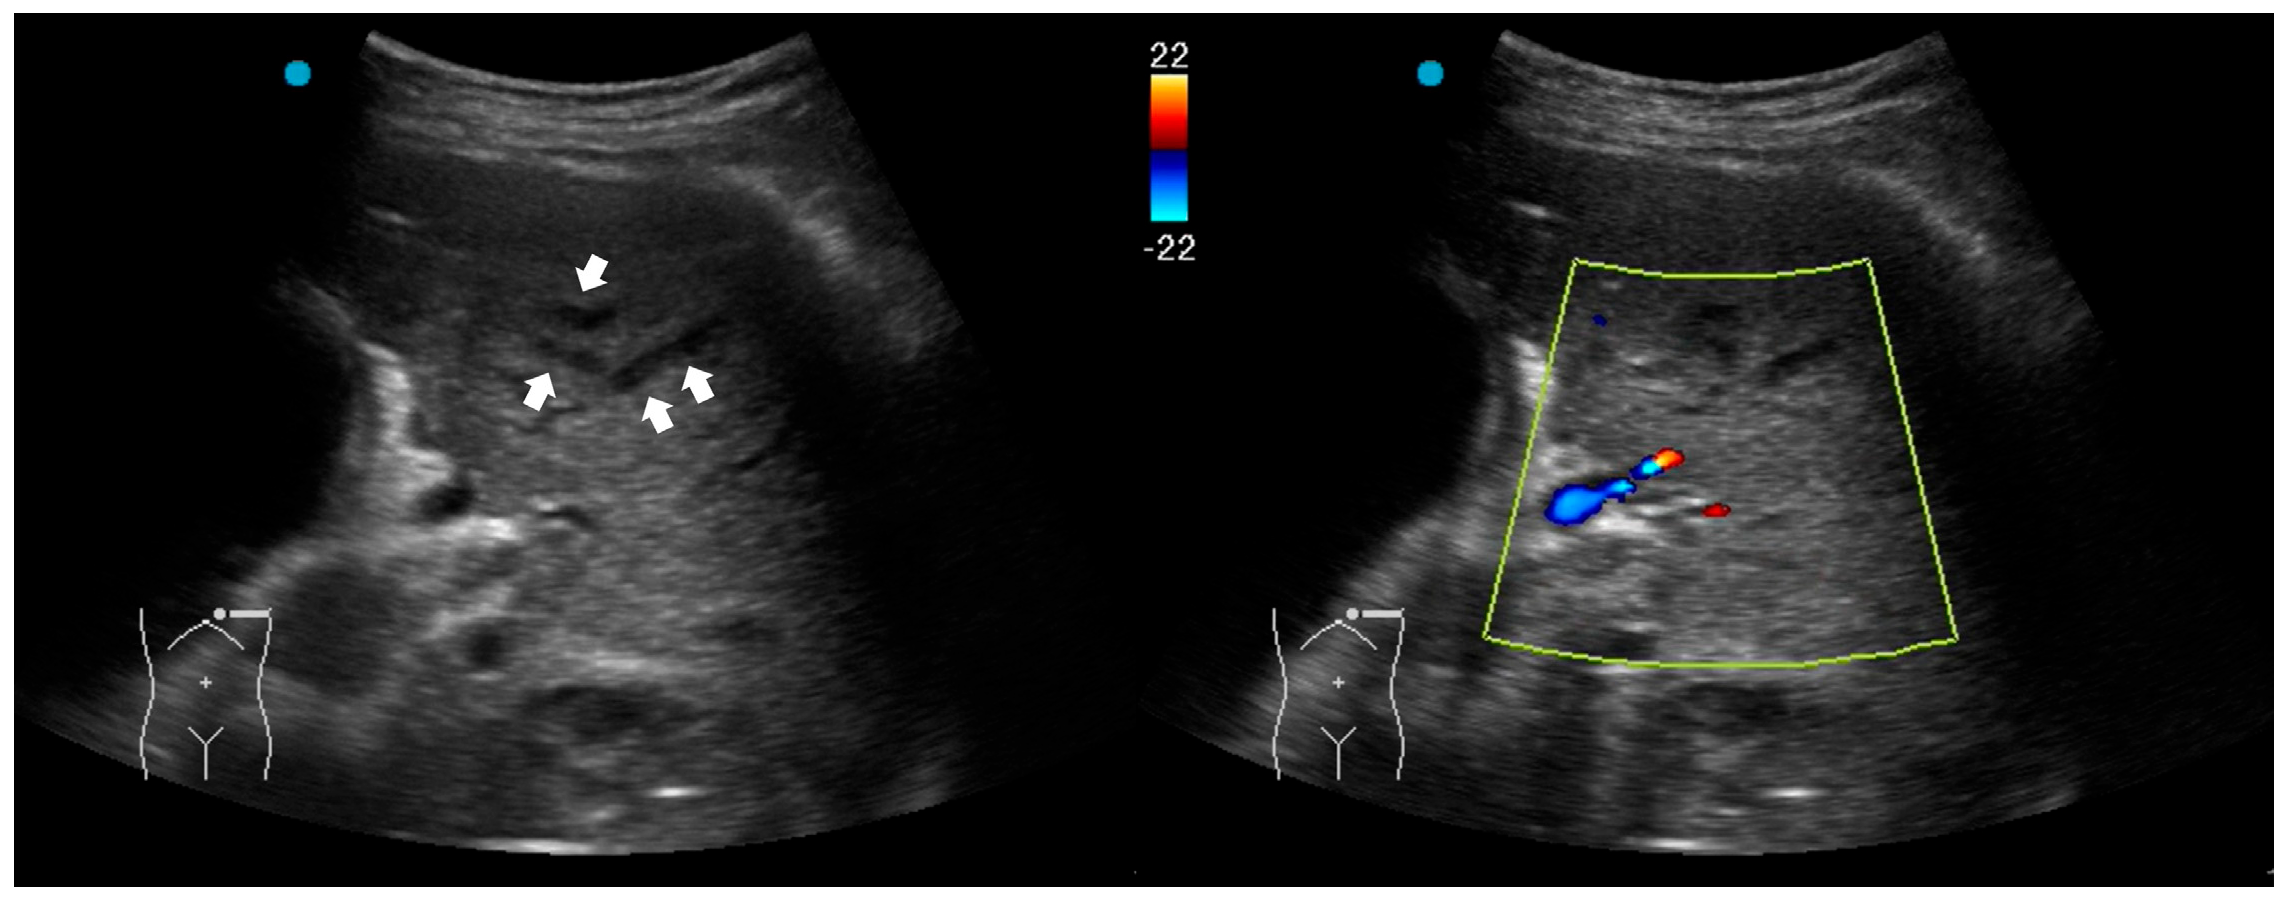

| Absence of color Doppler signals within consolidation (poor perfusion) | Necrotizing pneumonia |

| Hypoechoic lesions or microabscesses within consolidations | Necrotizing pneumonia |